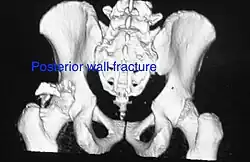

Posterior wall fracture as seen on 3-D CT scan -

| Posterior wall | This is the most common variety of acetabular fracture. It typically occurs due to dashboard injury; when a person travelling in a vehicle involved in a head-on collision, the force applied over the flexed knee travels along the femur bone to the head of the femur, breaking the posterior wall of the acetabulum. The head of the femur is dislocated outside the joint. | T shape | When a transverse fracture also had a vertical fracture line, it is called a T shape fracture. Here the innominate bone is broken in such a way that all three parts of it, the ilium, the ischium and the pubis are separated from one another. This is a three part fracture. Though both columns are broken, the weight bearing dome is still attached to the main part of the ilium and hence it is not a true fracture of both columns.

| Anterior wall | This fracture is uncommon, typically occurring when the injuring force is applied from the side, against the greater trochanter of the femur bone, as in a fall on the side or being hit on the side. | Transverse + posterior wall | These fractures are extension of elementary fractures. With involvement of posterior wall, the difficulty in treatment increases. These fractures are rarely amenable to non-surgical treatment. Due to posterior wall fracture, the hip is usually dislocated posteriorly, requiring immediate reduction of dislocation and surgical reconstruction after few days.